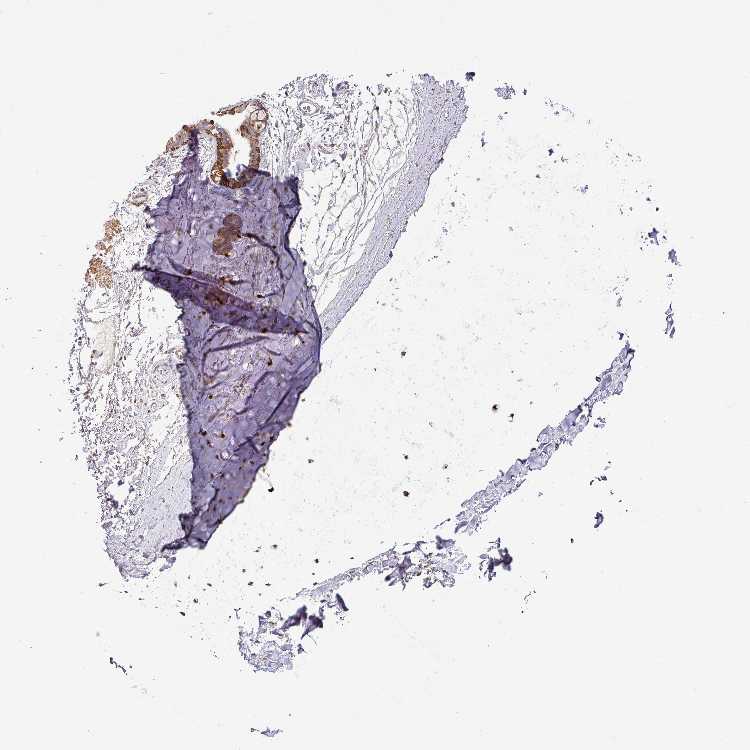

SOFT TISSUE 1 - Antibody stainingi

Antibody staining in the annotated cell types in the current human tissue is reported as not detected, low, medium, or high, based on conventional immunohistochemistry profiling in selected tissues. This score is based on the combination of the staining intensity and fraction of stained cells.

Each image is clickable and will lead to virtual microscopy that enables deeper exploration of all samples and also displays staining intensity scores, fraction scores and subcellular localization as well as patient and tissue information for each sample.

Antibody HPA001794

Chondrocytes High

Fibroblasts Low

Peripheral nerve Not detected